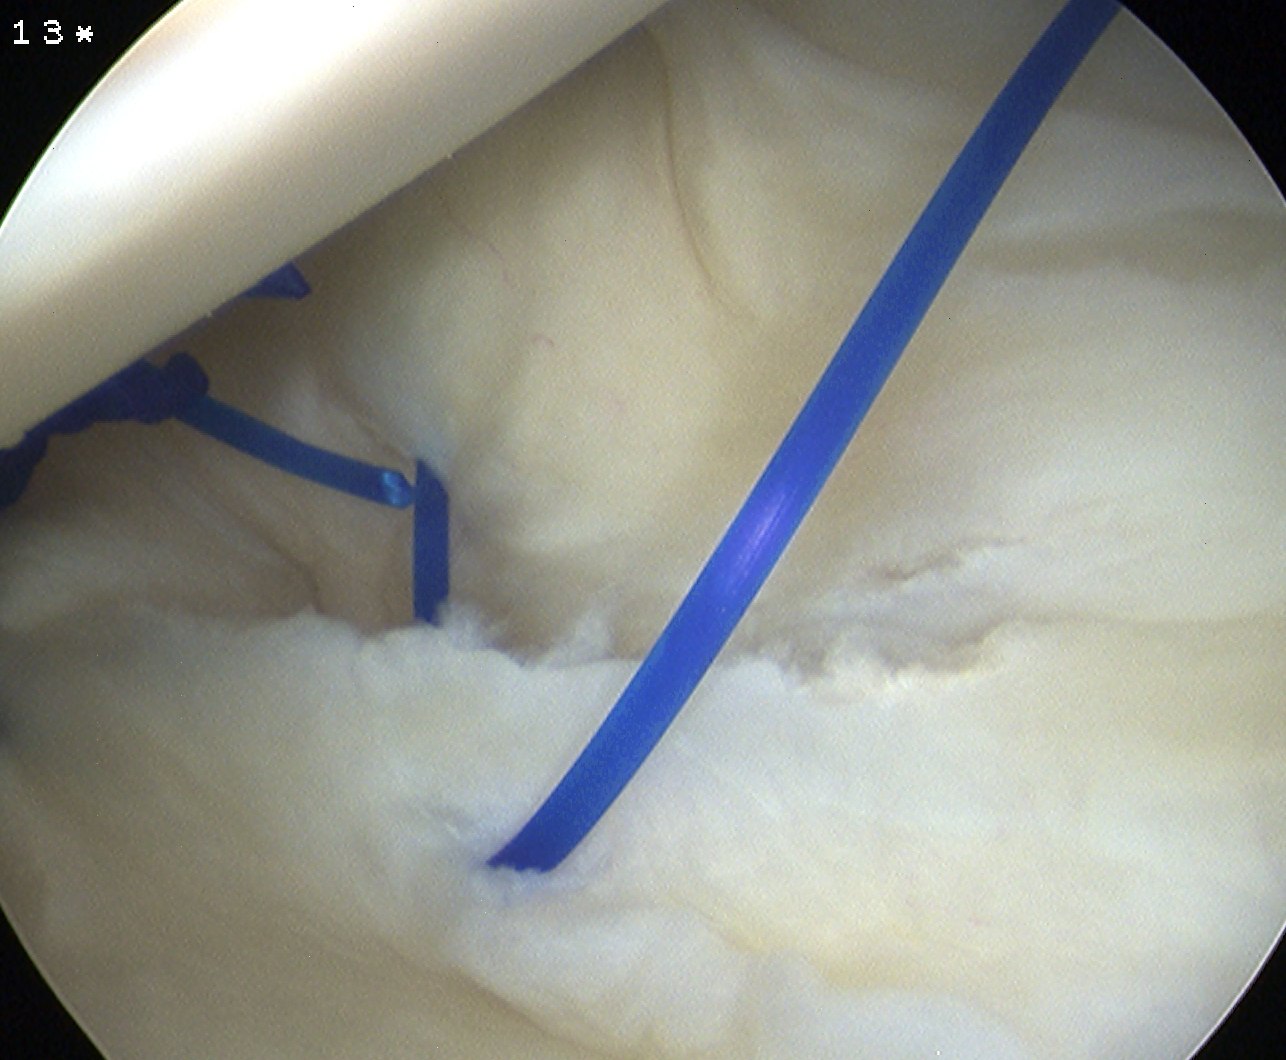

Anterior capsular plication with suture anchors

Posterior capsular plication

- option 1: Suture plicate capsule to labrum

- option 2: Anchors in glenoid and use to plicate capsule to labrum

Posterior capsular plication with suture anchors